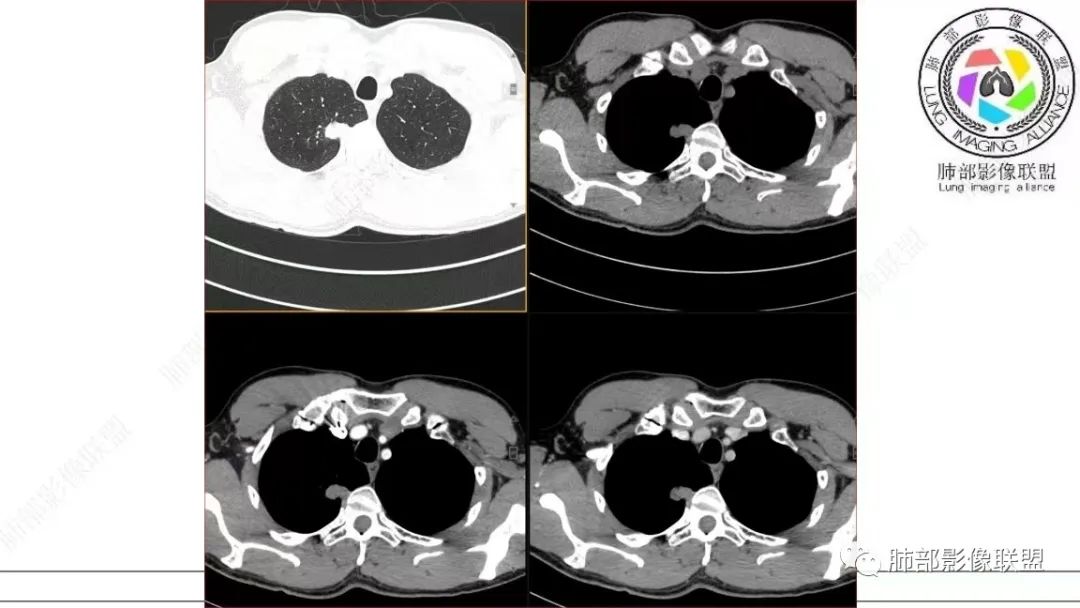

飞鹰行动:中年男性,右肺上叶不规则病灶,与胸膜粘连,多发长毛刺,周围模糊的磨玻璃影,相邻胸膜增厚,增强病灶中度以上强化,内见血管影,没有重建图像,感觉病灶符合良性病变征象多一些,考虑炎性病变,OP?

小兜:男,50岁,体检发现右肺上叶胸膜下不规则软组织结节,分叶,长毛刺,与胸膜相连,胸膜增厚,渐进性强化,强化不均匀,内部可见小灶状低强化灶,内部血管穿行。首先考虑肉芽肿性病变,鉴别腺癌

衡妈:中年男性,右肺上叶尖段不规则实性病灶,边缘多深分叶局部形似并见数条长毛刺,与胸膜面数条牵拉中年男性,右肺上叶尖段不规则实性病灶,边缘多深分叶局部形似枫叶,侧胸膜局部幕状增厚,病灶增强后不均匀中等强化。考虑恶性肿瘤,腺癌可能,鉴别炎性肉芽肿(结核)、炎性肌纤维母细胞瘤。

谢加平:右肺上叶尖段内侧胸膜下分叶状结节,不规则,见尖角状凸起,边缘支气管锥形中断,实性不均匀强化,血管进入增粗和集血管束特点,宽基底胸膜牵拉,形成兔耳征,冠状面结节外侧见指头状凸起,恶性特点明显,支持浸润性腺Ca。

仔细看,里面是有低密度的。平扫CT值也很低,才16HU。

增强也很有特点。这些低密度,是有延迟强化特点的。

平扫低密度,就这个病变而言,我们最容易想到的:干酪性坏死、黏液。而延迟强化。所以这个病变是不符合干酪性坏死的表现的。很多平直凹陷的地方,与胸膜宽基底接触,是否存在胸膜牵拉不详,需重建看看。说明这个病变是有收缩力的。里面含有一部分纤维。当然,含有纤维的,肿瘤的肌成纤维可以,上皮间质转换可以,慢性炎也可以,好多病变里面可以有纤维。干酪样坏死,是不会强化的。延迟强化,肉芽肿可以,纤维比较多的或者黏液多的也可以。